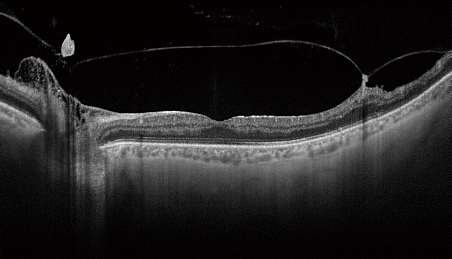

Уникальное сочетание нового механизма получения ОКТ-снимков SWEPT Source и сканирующего луча в инфракрасном диапазоне (1050 нм) позволяет получить качественный ОКТ снимок структур заднего отрезка глаза: стекловидного тела, сетчатки, хороидеи и склеры – на одном скане. Эта особенность сокращает время исследования за счет отказа от получения дополнительных снимков для получения снимков высокой четкости.

Большая проникающая способность инфракрасного излучения позволяет получить снимки даже в случае наличия помутнений в прозрачных средах глаза (катаракта, кровоизлияния и т.д.).

Прибор позволяет получать ультраширокие сканы 12 × 9 мм и 12 × 12 мм, позволяющие оценить состояние диска зрительного нерва и макулы за одно исследование.